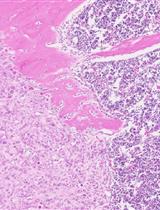

Figure 3. Formation of retinal vein-associated vascular tufts following TIE2 attenuation. (A) Tamoxifen intragastric administration and analysis scheme. (B) Mouse eyeballs were collected with the cornea, sclera, choroid, and pigment layer removed. Retinas were cut by four radial incisions for further immunohistochemical analysis. (C) Analysis of retinal blood vessels for PECAM-1 (green) and EphB4 (red) in TekiUCKO and control mice at P21. Note that TIE2 insufficiency leads to vascular tuft formation along retinal veins. Arrowheads indicate arteries, and arrows indicate veins. Scale bar: 100 μm in C.